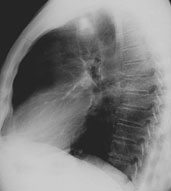

Ein 58-jähriger, sportlich aktiver Mann sucht Sie in der Sprechstunde auf. Er klagt über eine Leistungsminderung und Husten mit etwas weisslichem Auswurf seit ca. 2-3 Wochen. Dazu subfebrile Temperaturerhöhung.

In der Anamnese erfahren Sie, dass der Patient früher geraucht hat (30 packyears), seit 10 Jahren allerdings nicht mehr. Kardiopulmonale Vorerkrankungen werden verneint. Die Lungenauskultation zeigt keine pathologischen Befunde.

Sie beschliessen, ein Thorax-Röntgenbild durchzuführen:

Wie beurteilen Sie das Röntgenbild in Kombination mit der Klinik?